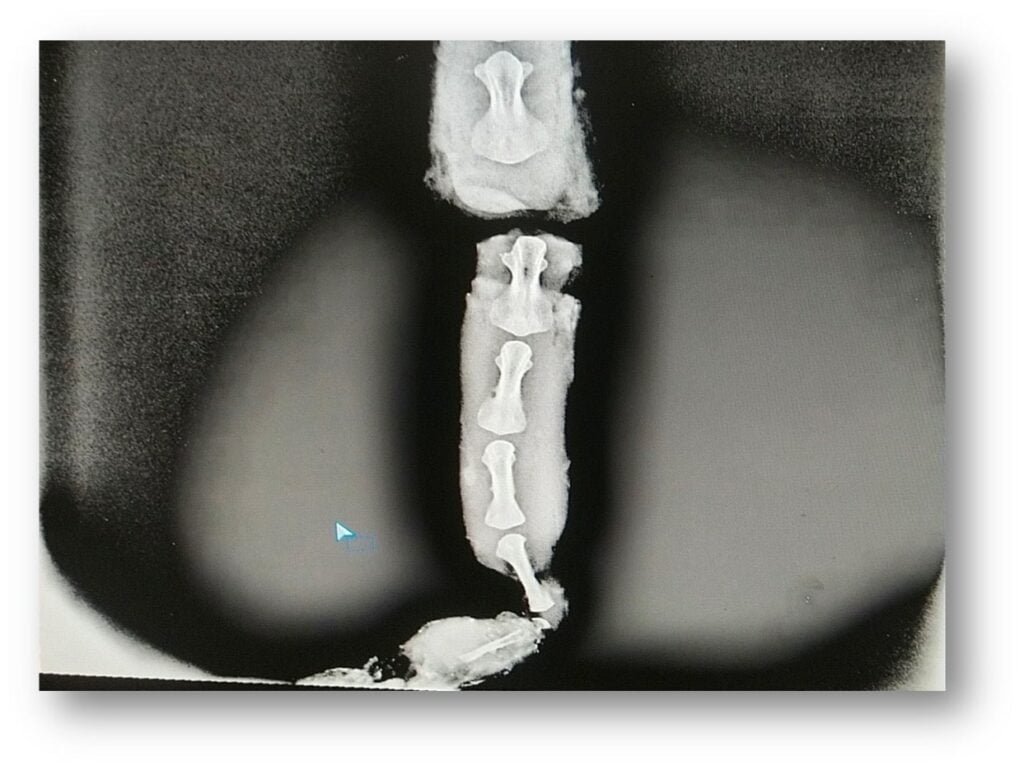

Veterinary Surgery and RadiologyStructures or organs can be evaluated more effectively for their size, shape and position by use of contrast radiography in animals.